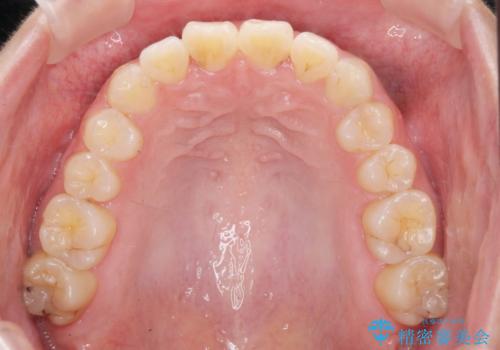

- 前歯のねじれを改善したい、と矯正治療を希望され来院されました。

上下の歯のがたつきを改善するマウスピース矯正治療と、下顎に見られる大きな骨隆起を外科的に除去する治療計画を進めていきます。

歯並びが改善したとともに、骨隆起を除去したことで舌をしまうスペースも増え安定した口腔内環境を確立することができました。